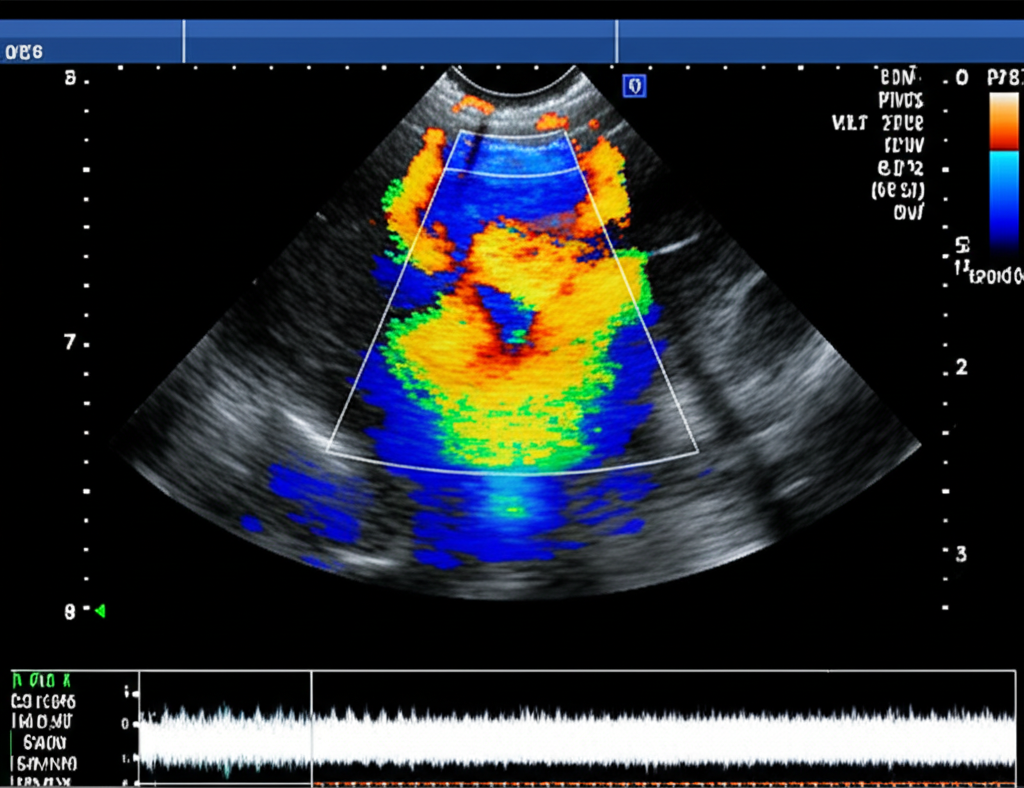

Não é pouca coisa. Estamos falando da tecnologia que permite ao médico “enxergar” dentro dos seus vasos sanguíneos em tempo real, sem cortes, sem dor. É a ferramenta número um para diagnosticar desde varizes, que atormentam tanta gente, até condições silenciosas e perigosíssimas como a trombose venosa profunda e as placas de gordura que podem entupir artérias e causar um infarto ou derrame.

• Elastografia: Uma técnica que mede a “dureza” de um tecido, ajudando a diferenciar um coágulo antigo de um novo, ou uma placa de gordura mais perigosa de uma mais estável.

• Ultrassom com Contraste (CEUS): Microbolhas injetadas na veia que melhoram a visualização de vasos muito pequenos ou de fluxo sanguíneo muito lento, algo antes quase impossível de ver.